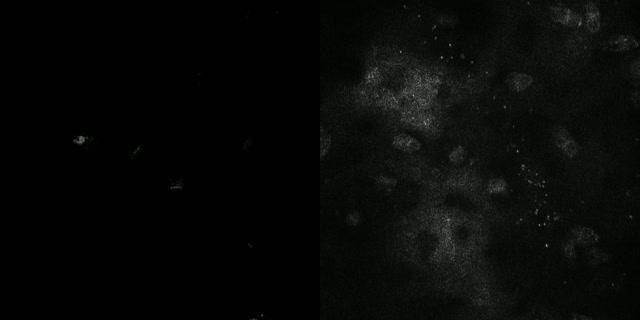

video: Real-time image of CGCs filmed at 15 frames per second. CFM imaging is shown in left and CRM imaging shown in right. CFM allows real-time imaging of the goblet cells with higher image contrast than the existing imaging methods.

In the meanwhile, there has been a report on using confocal reflection microscopy (CRM) to image conjunctival goblet cells. The assessment is non-invasive, yet, it provides relatively low image contrast and, is hard to obtain precise results.

Also, the moxifloxacin-based fluorescence imaging of conjunctival goblet cells was tested in a mouse model. Moxifloxacin was injected into a mouse and it was examined under the CRM after one to two minutes of injection. The team verified that a bright cluster of conjunctival goblet cells on the surface of conjunctiva was shown. In comparison with the existing CRM, this fluorescence imaging method demonstrated high image contrast and could do real-time imaging at 10 frames per second.